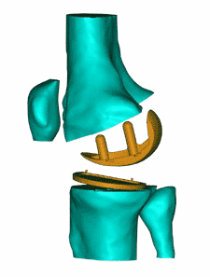

(Foreground Image) Complete knee assembled in Geomagic Wrap overlaying a fluoroscopic image of the knee. Banks’ lab can calculate the three-dimensional relative motion of the artificial knee components through image matching.

Total knee replacement (TKR) is a common remedy for the painful and debilitating effects of knee joint osteoarthritis, a condition which occurs when the cartilage covering the ends of the tibia (shin bone) and femur (thigh bone) begins to degenerate. In TKR surgery, the cartilage bearing surfaces of the tibia and femur are replaced with artificial surfaces. The femur is fitted with a metallic bearing surface, and the tibia is fitted with a metallic base plate into which a plastic insert is snapped. While TKR usually restores some mobility, problems related to wear of the plastic insert typically limit implant life span to roughly 20 years - possibly less for more active patients.

For more accurate measurements of knee joint motion, Dr. Scott Banks uses a dynamic X-ray procedure called fluoroscopy. When studying artificial knees, Banks obtains CAD models of the implant components from the manufacturer. He then uses custom software to match the 3D CAD models to each 2D fluoroscopic image as though he were orienting an object to a photograph of its shadow.

Since the CAD models have embedded coordinate systems, the image-matched components are used to quantify the 3D motion of the patient’s knee under real-life loading conditions, such as walking and climbing stairs.

Fregly also uses Geomagic Wrap to convert polygonal surface models, which are adequate for image matching, into the mathematical surface models necessary for contact stress analysis. Such models use a “quilt” of rectangular surface patches to create a mathematical representation of the geometry. Since the “seams” between the surface patches can complicate contact analyses, Fregly uses the software to merge all patches on a contact surface into a single patch. The same process is used to “resurface” CAD models of artificial knees for contact analysis. Any deviation between the polygonal model and the final mathematical surface representation can again be determined with Geomagic Wrap’s tolerance functionality.

Segmented CT scan slices are stacked to form a point cloud model of the femur

Geomagic Wrap is used to create a detailed polygonal model from the point cloud data.

The polygonal surface deviates from the point cloud model by no more than 0.2 millimeters.